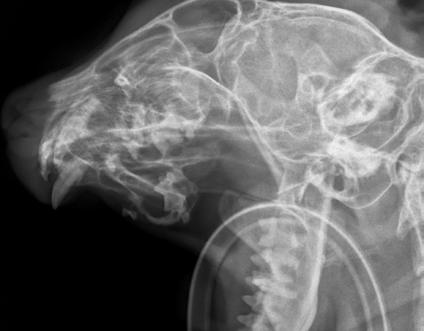

An 8-month-old female desexed Labrador retriever cross presented for a 4–6-week duration of left forelimb lameness.

On clinical exam, there was mild pain on manipulation of both shoulder joints.

Q. What is your radiological diagnosis?